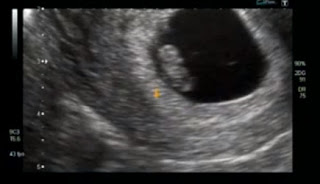

Preciso falar que foi a maior emoção da minha vida? Não né..mas eu falo mesmo assim, depois do positivo esse foi o momento mais feliz que vivi. Ver o coração pulsando e escutá-lo é algo de outro mundo, as grávidas piram!! E o marido então? Nossa..ficou todo bobo!!

Nos cálculos da ultra, meu baby está com 7 semanas e 2 dias, mas estou usando a data da minha GO, 6 semanas e 5 dias. Ainda não sei qual é a melhor data para considerar. O médico disse que está tudo bem, batimentos normais (como bate forte, né?), sem deslocamento e só tem 1 bebê..kkkk

Já assisti o vídeo umas 1293108 vezes, mostrei para a família também e foi a maior choradeira..kkk!!